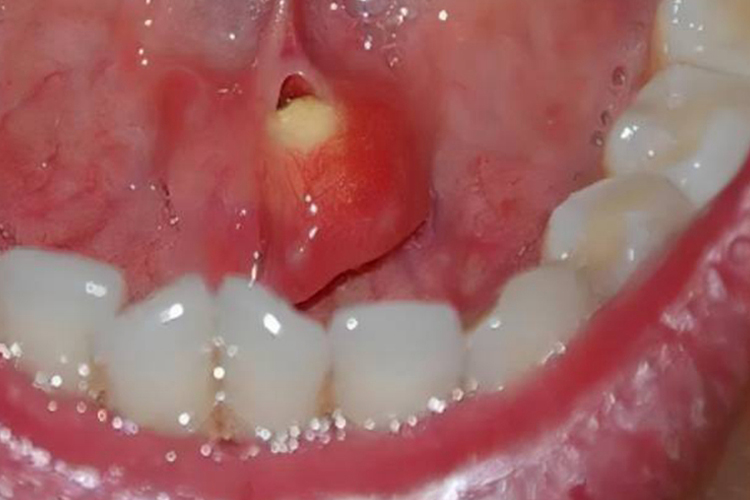

舌下肉阜是舌系带两旁乳头状凸起的组织,当舌下肉阜肿大可出现不同程度的异常增生。

小的涎石一般不造成唾液腺导管阻塞,无症状。典型的下颌下腺导管结石为长圆形,呈枣核状。小者如小米粒大小,可被排送到舌下肉阜的导管口,大者可使导管增粗,出现舌下肉阜肿大的现象。